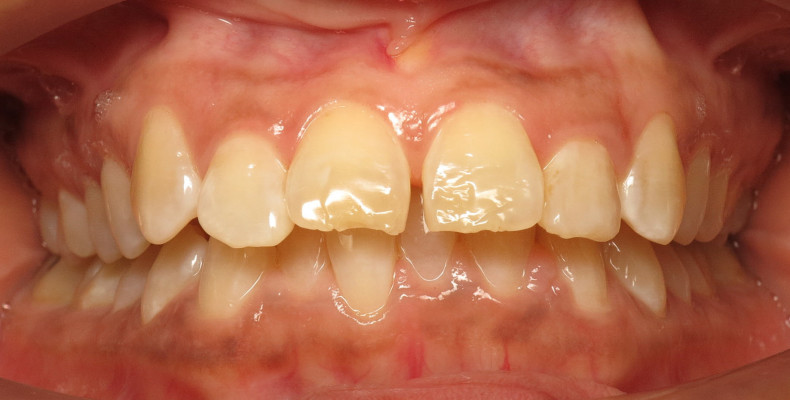

Sehr häufig gehen anteriore Tiefbisse mit einer Klasse II-Okklusion einher. So auch bei dieser 47-jährigen Patientin, bei der die starke Verschlüsselung der Okklusion zu einer Kompression beider Kiefergelenke und funktionellen Beschwerden geführt hat. Sie stellte sich bei uns in der kieferorthopädischen Praxis mit Nackenbeschwerden, Kopfschmerzen sowie reziprokem Kiefergelenkknacken rechtsseitig vor. Ihr Hauptanliegen war daher eine funktionelle Verbesserung, sie wünschte sich aber auch eine ästhetische Zahnkorrektur mittels Alignerbehandlung. Die Patientin störte sich ästhetisch vor allem an den aufgefächerten Oberkieferfrontzähnen. Eine kieferorthopädische Behandlung war bereits im Jugendalter erfolgt. Die Funktionsanalyse ergab eine Diskusdislokation rechtsseitig bei Kompression beider Kiefergelenke. Die Mundöffnung war eingeschränkt und erfolgte wie der Mundschluss mit Deviation. Der extraorale Befund (Abb. 1a–c) zeigte ein konvexes Gesichtsprofil bei deutlich verkleinertem Nasolabialwinkel (90,8°). Zudem waren Impressionen der Oberkieferzähne in der Unterlippe erkennbar.

Der intraorale Befund (Abb. 2a–e) sowie die Modellanalyse (Abb. 3a–e) zeigten neben dem Diastema mediale im Oberkiefer vor allen Dingen eine Anteinklination und Supraokklusion beider Fronten. Besonders anterior wiesen beide Zahnbögen eine transversale Enge auf. Dies zeigte sich in einem deutlichen Unterkieferfrontengstand mit Labialkippung des Zahnes 41. Neben Abrasionen und Schlifffacetten, vor allem in der Front, waren auch vereinzelt Gingivarezessionen erkennbar. An Zahn 11 lag eine Schmelzfraktur der Inzisalkante vor. Durch die zwangsgeführte Laterognathie ergab sich eine Mittellinienverschiebung nach rechts von 3 mm. Eine beidseitige Distalokklusion bei vergrößerter sagittaler (6 mm) und vertikaler (5 mm) Stufe war erkennbar. Aufgrund der deutlichen transversalen Zahnbogenenge im Unterkiefer ergab sich links eine Tendenz zum Scherenbiss.